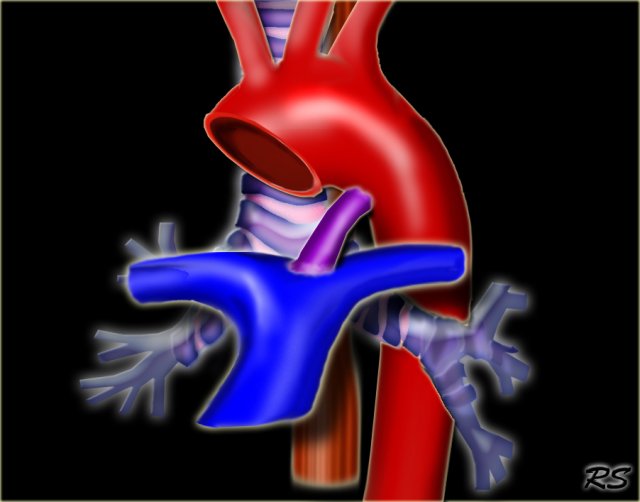

Pulmonary Sling Pulmonary Sling

In pulmonary sling the left PA originates from the right PA and courses between the esophagus and the trachea, where it compresses the right main bronchus.

Pulmonary sling is seen more frequent in children as it is more symptomatic than in adults, because the chest is smaller, but you can also encounter it in adults.